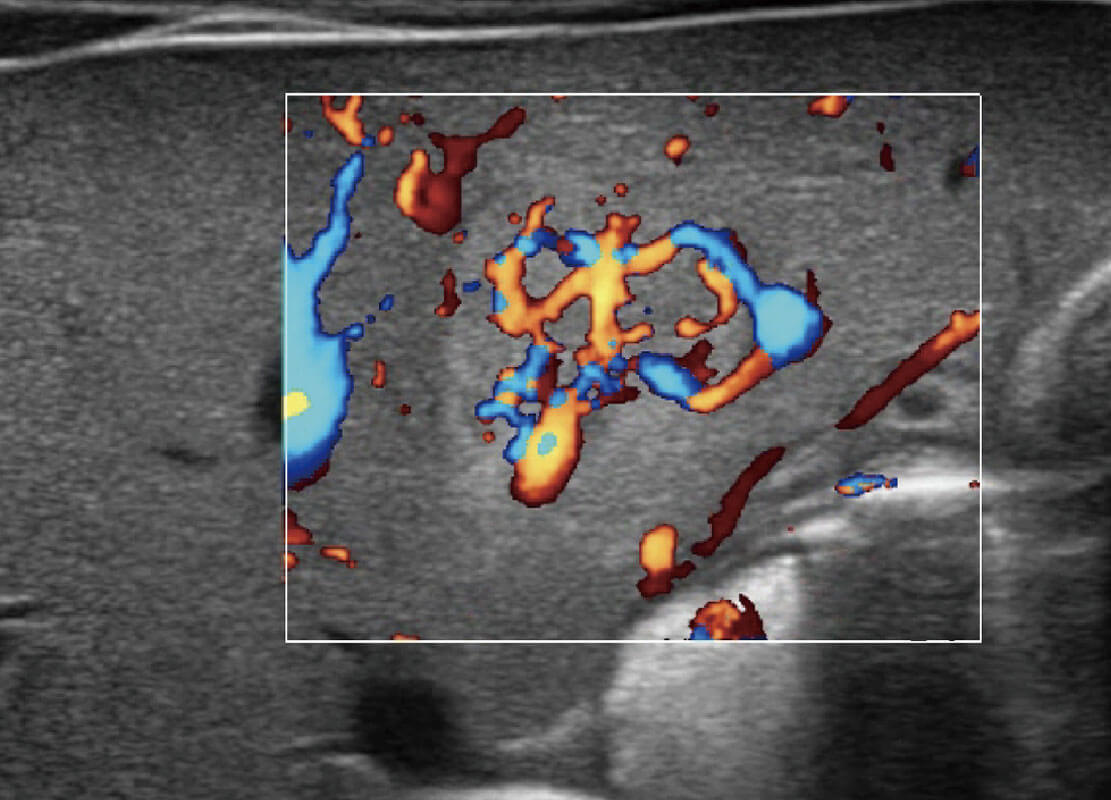

乳腺癌显微血流

新生儿肝血管癌